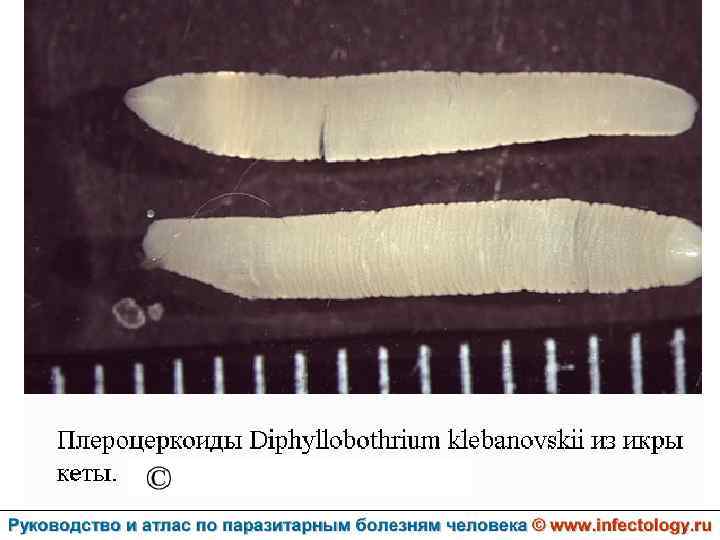

Дифиллоботриоз (шифр по МКБ 10 – B 70. 0) – зоонозный биогельминтоз с хроническим течением, характеризующийся нарушением функций верхнего отдела пищеварительного тракта, а при тяжелом течении - развитием анемии.